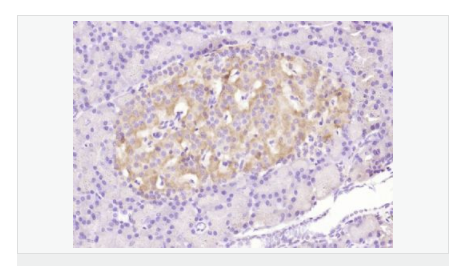

| 產(chǎn)品應(yīng)用 | WB=1:500-2000 ELISA=1:5000-10000 IHC-P=1:100-500 Flow-Cyt=3μg /test (石蠟切片需做抗原修復(fù)) not yet tested in other applications. optimal dilutions/concentrations should be determined by the end user. |

| 免 疫 原 | KLH conjugated Synthesised phosphopeptide derived from human Bax around the phosphorylation site of Ser184:TA(p-S)LT |